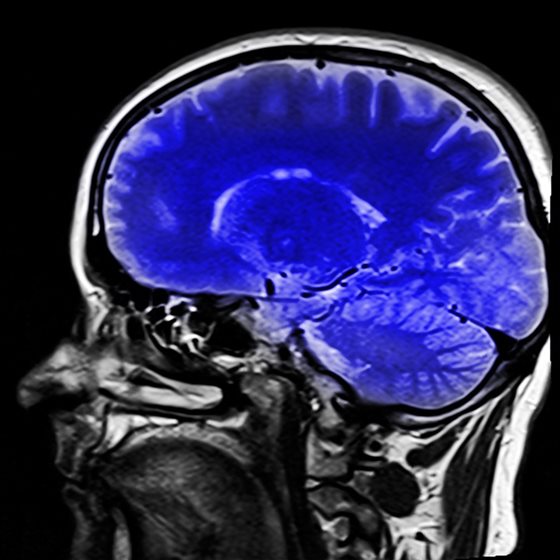

fMRI neurofeedback allows researchers to non-invasively analyse brain activity and identify which areas of the brain should receive increased activation.

In an article published by the prominent Nature journal, Dr Sokunbi explained how patients were given strategies to engage parts of the brain that can cause depression and were given instant feedback from an MRI scan.

Through the signals shown by the MRI machine, patients were able to see how their brains reacted to the treatment and the effect that it had on their depression.